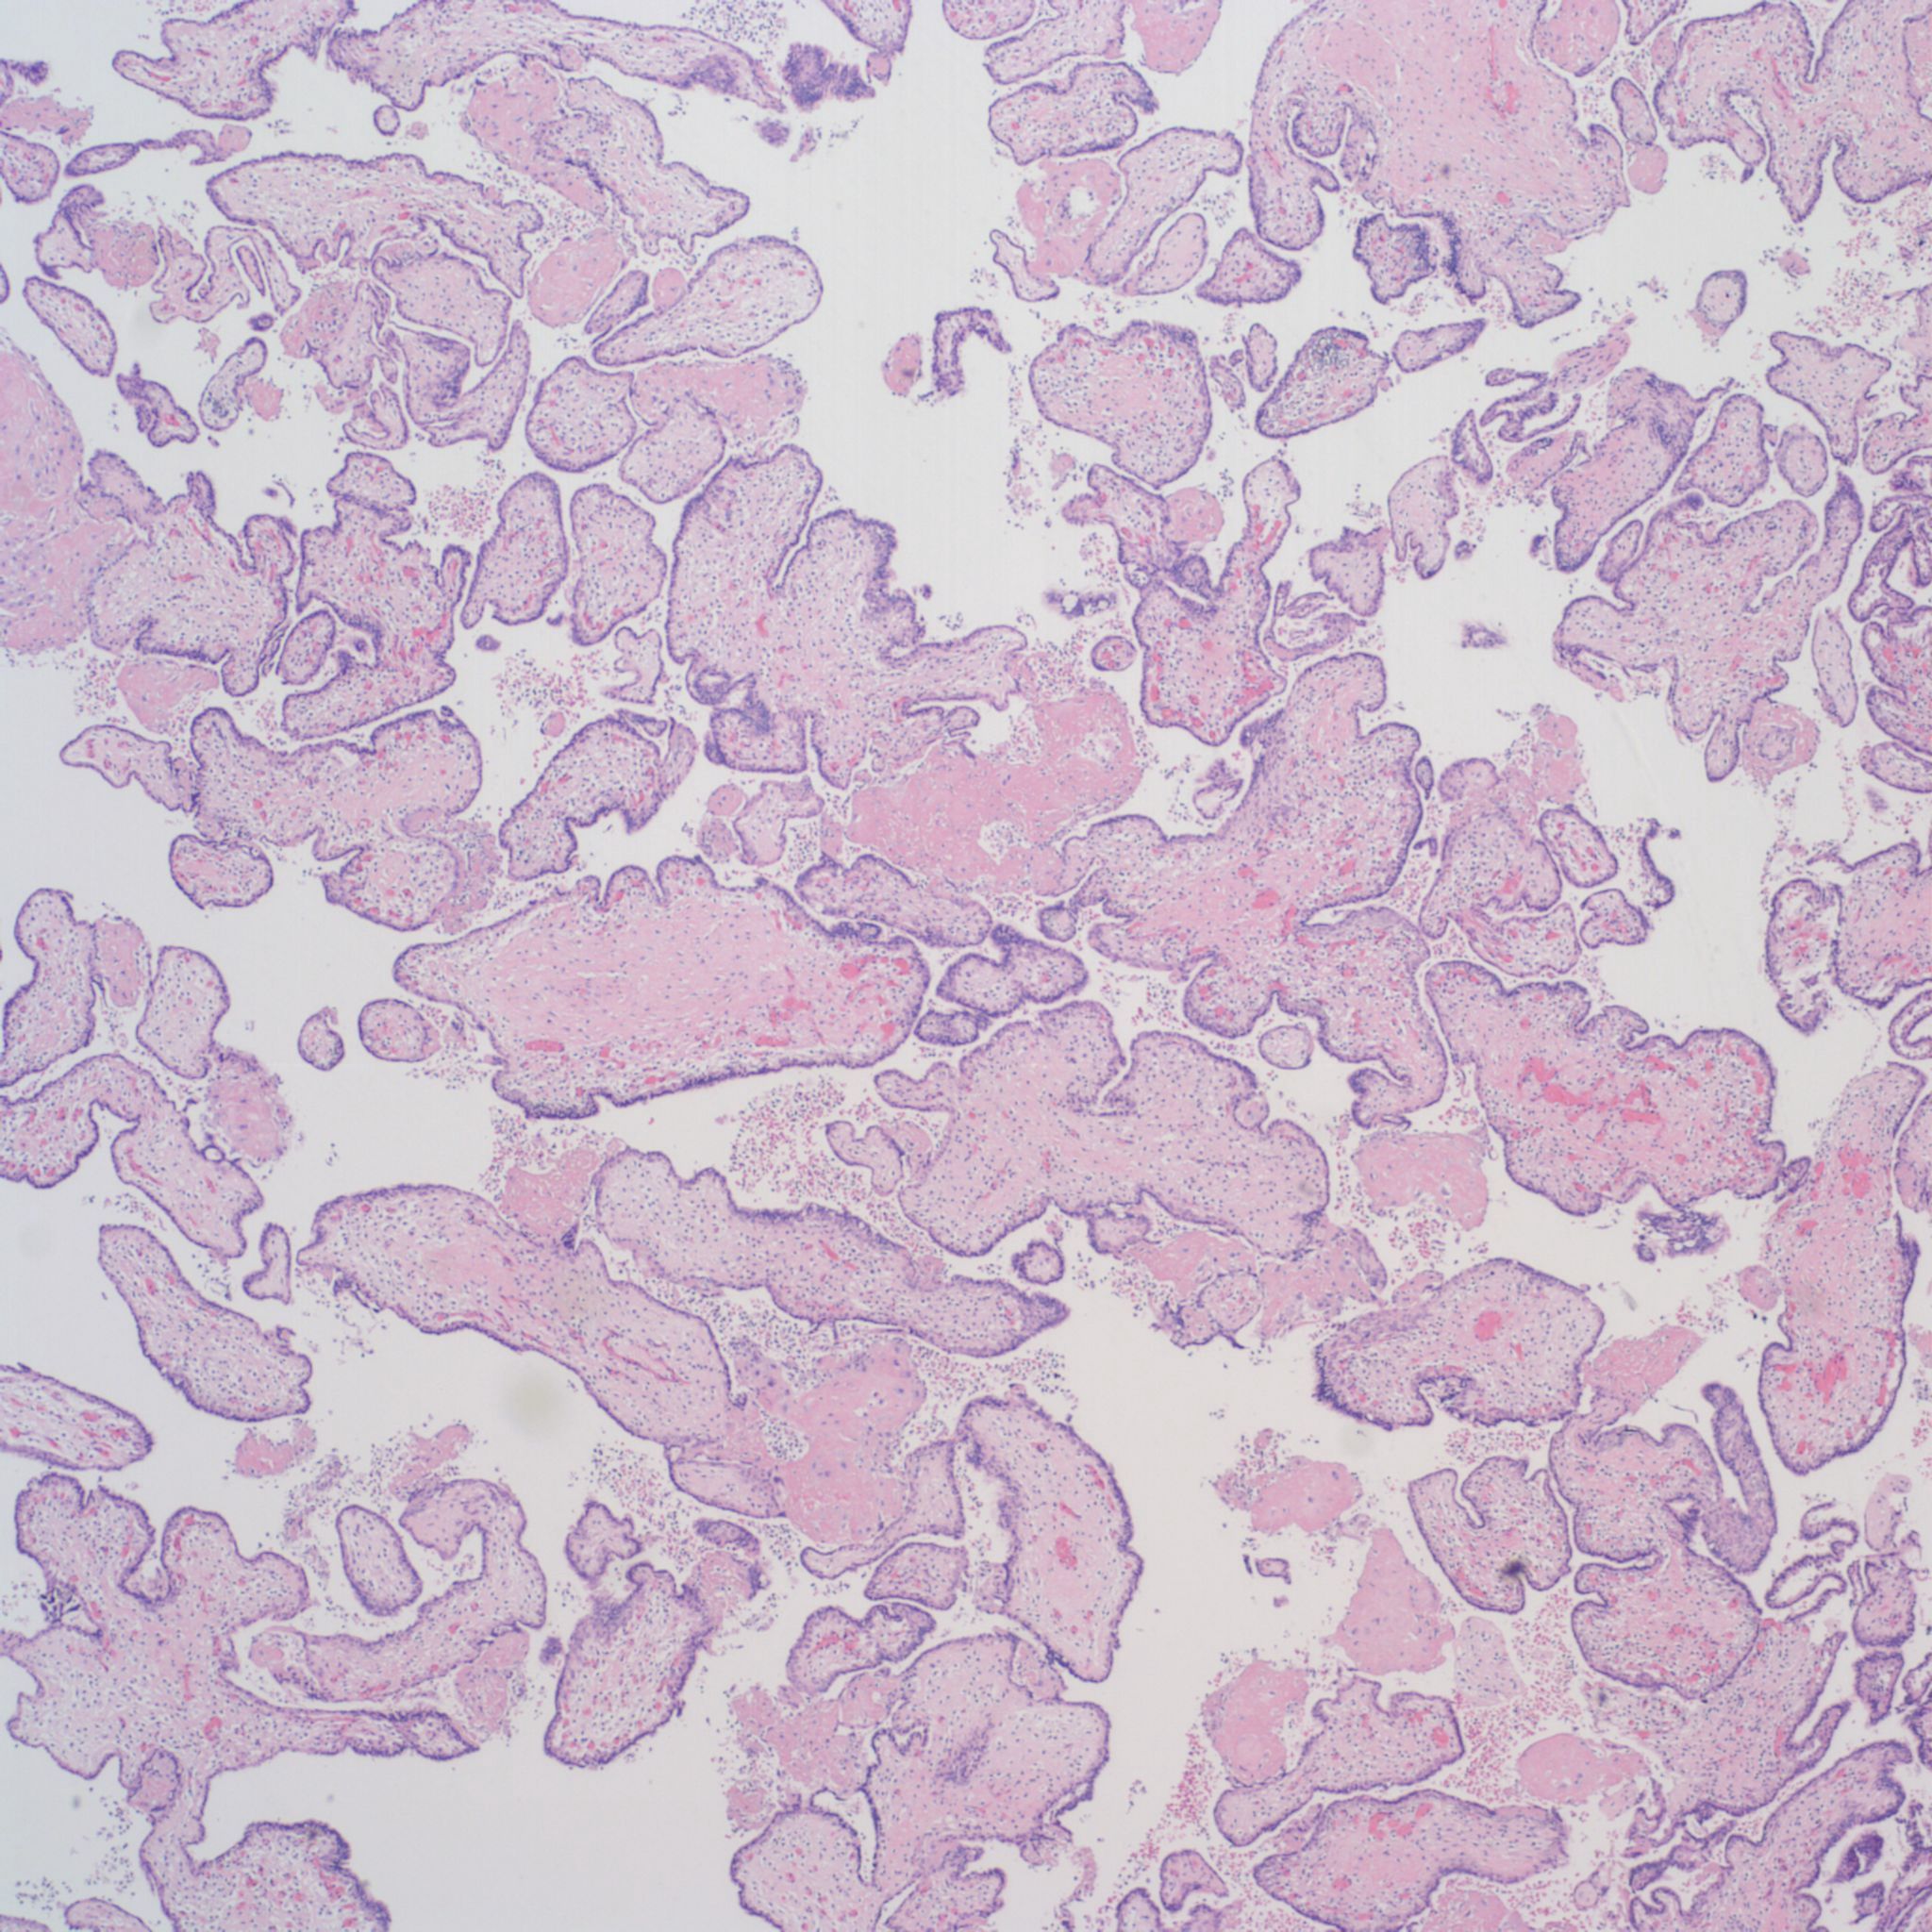

High Grade (massive) CHIV

Low Grade CHIV (5-50% of the intervillous space occupied by monocytes)

There is a focus of intervillous fibrinoid with no definite cytotrophoblast that is not re-covered with syncytium suggestive of recent syncytial injury (F). (10x, H&E)